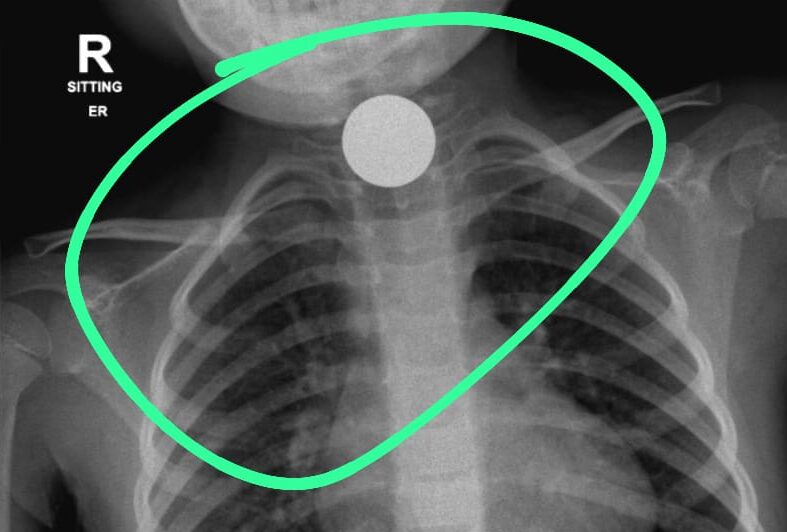

במקרה אחר, הובאה ילדה בת 4 אל בית החולים ובצילום רנטגן נמצאו בוושט של הילדה מטבעות כסף שגרמו לדחיקה של קנה הנשימה , דבר שמנע מהילדה לנשום כראוי.

אאג/ניתוחי ראש צוואר ועם רופאים בכירים נוספים, הוחלט כי יש צורך בניתוחים דחופים כדי למנוע סכנה לחייהם של שני הילדים.

הניתוח הראשון, של הילדה בת ה 4, נעשה בראשותם של ד"ר עופר גליק וד"ר ירדן טננבאום ממחלקת א.א.ג/ניתוחי ראש צוואר; הניתוח השני, של הילדה בת ה 7, נעשה הבוקר (יום ד) על ידי ד"ר חני טאף. לשמחת כולם, הניתוחים הסתיימו בהצלחה. מטבעות הכסף וחלקי המשחק הוצאו בשלמותם והילדות הועברו להמשך טיפול והשגחה במחלקת הילדים של ביה"ח הציבורי אסותא אשדוד.